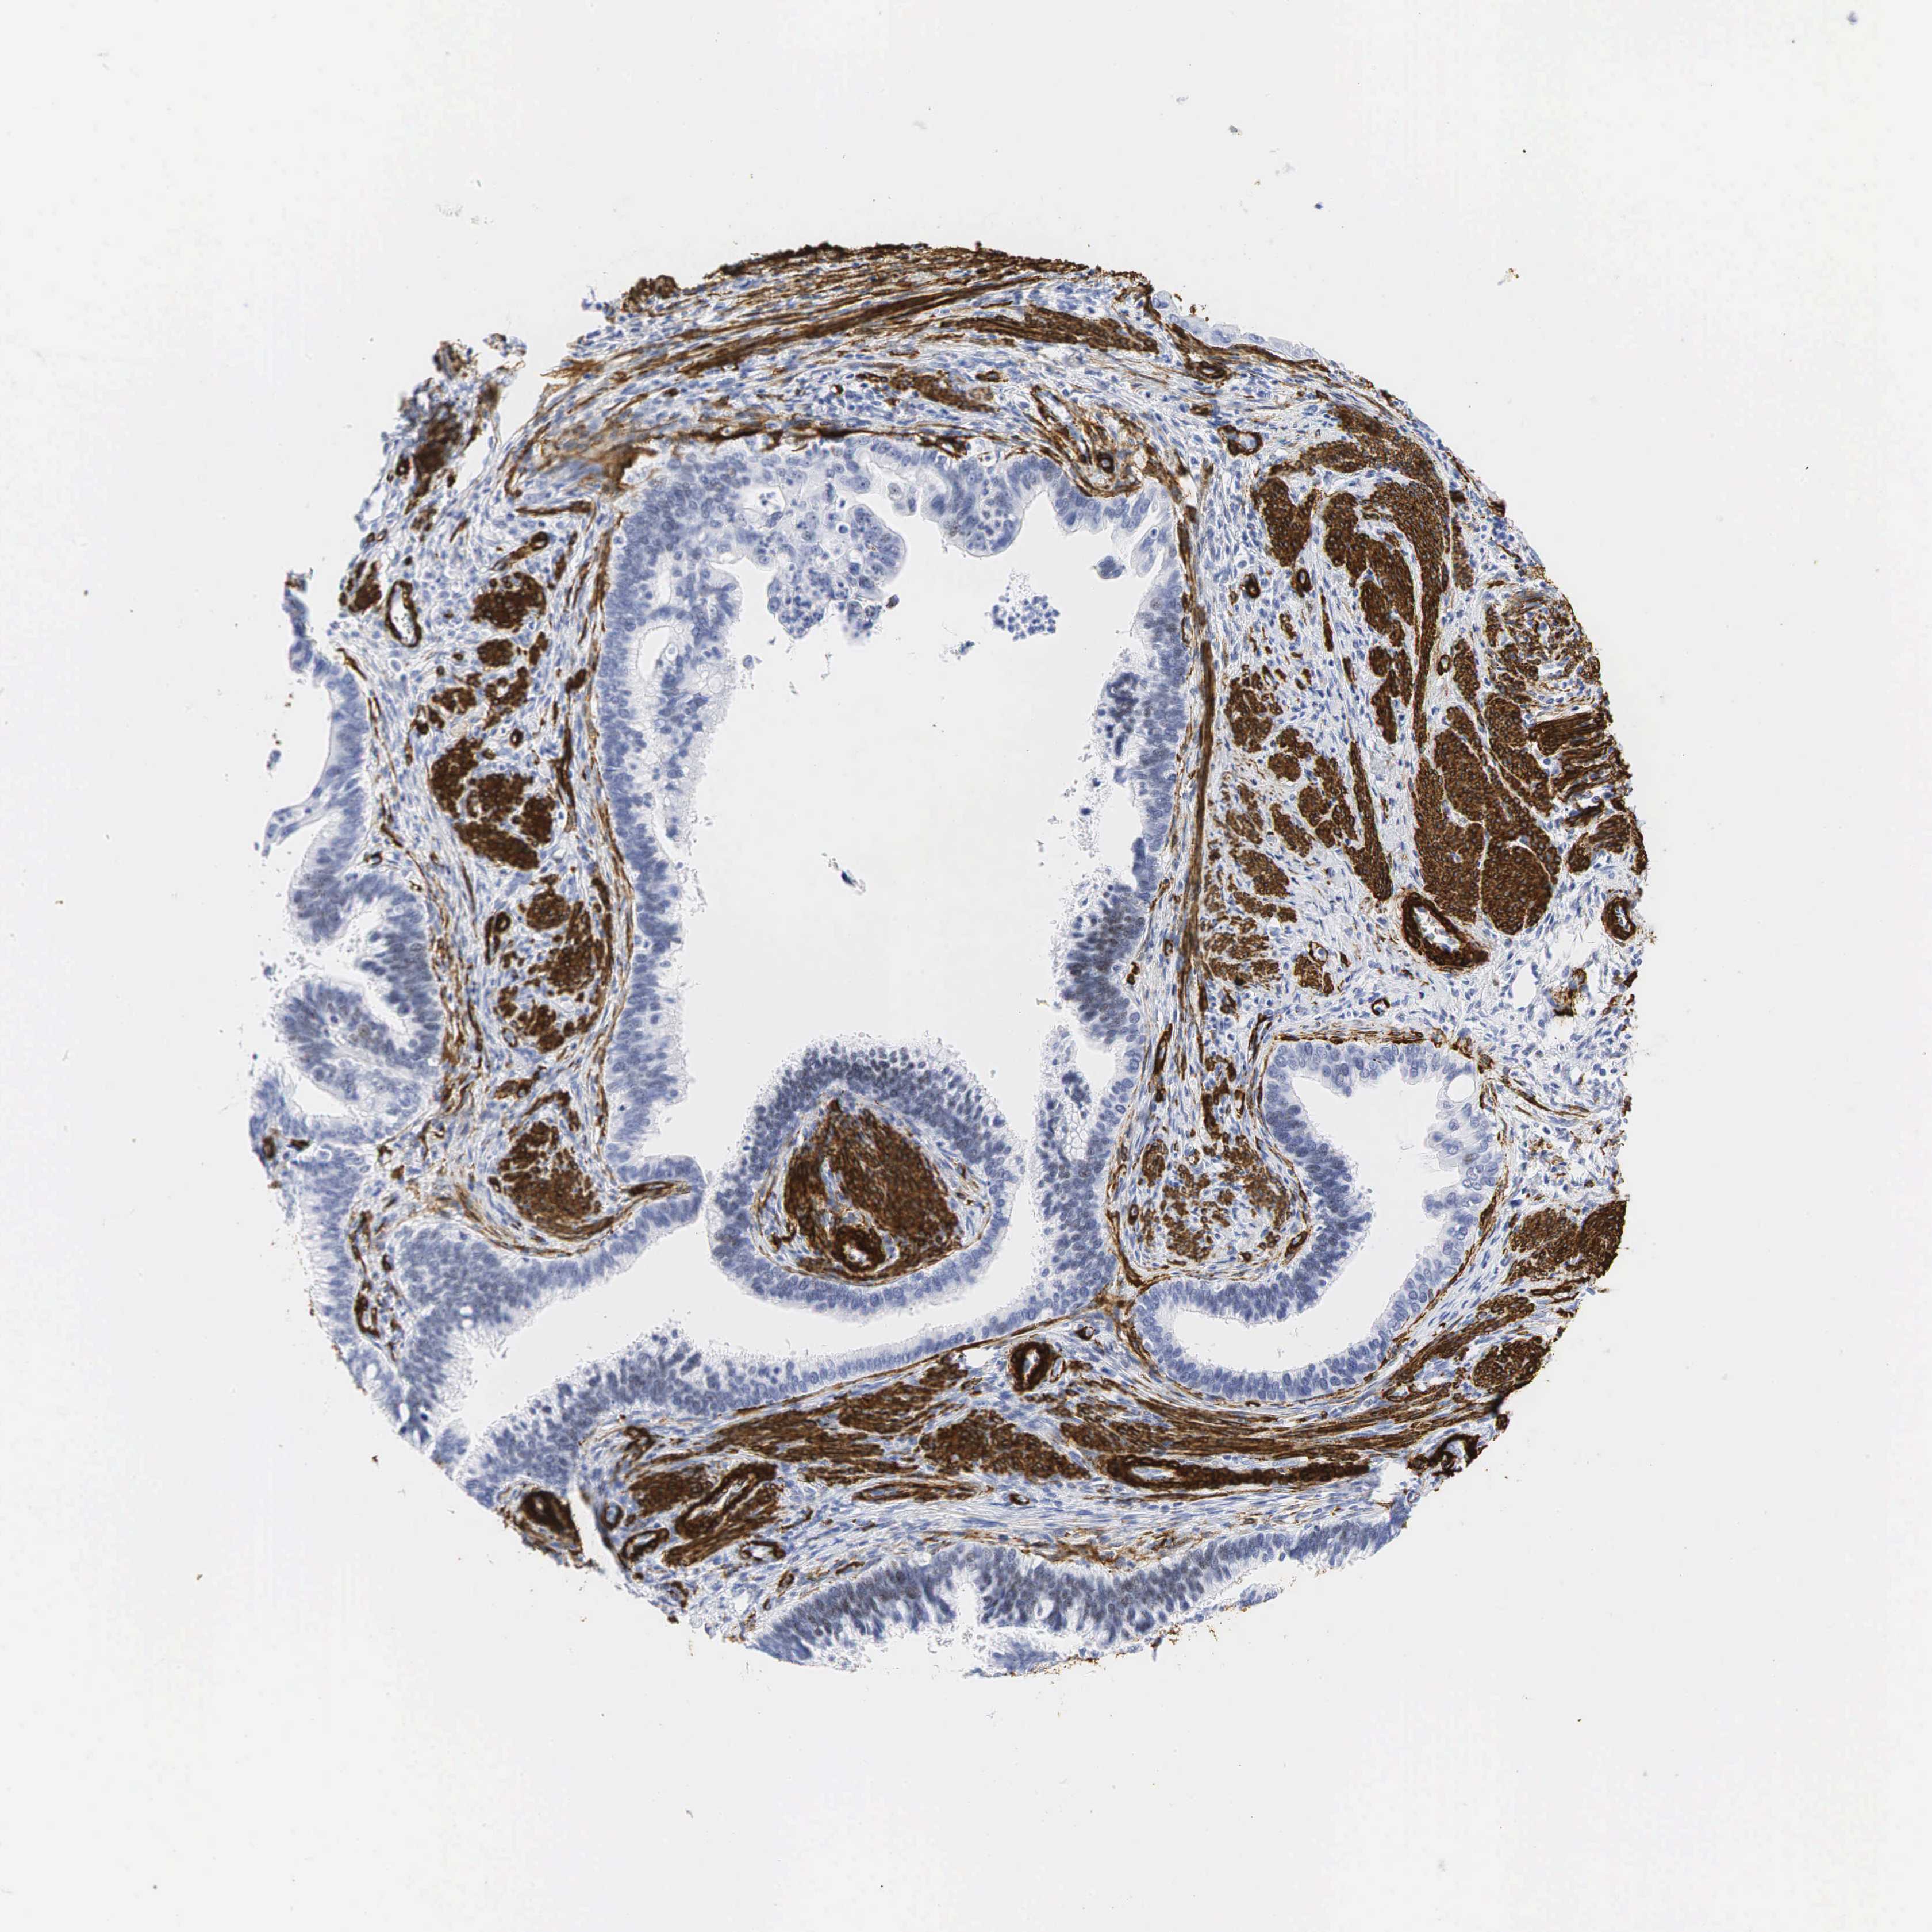

CERVICAL CANCER - Protein expressioni

A mouse-over function shows sample information and annotation data. Click on an image to view it in a full screen mode. Samples can be filtered based on level of antibody staining by selecting one or several of the following categories: high, medium, low and not detected. The assay and annotation is described here.

Note that samples used for immunohistochemistry by the Human Protein Atlas do not correspond to samples in the TCGA dataset.

Antibody stainingi

Antibody staining in the annotated cell types in the current human tissue is reported as not detected, low, medium, or high, based on conventional immunohistochemistry profiling in selected tissues. This score is based on the combination of the staining intensity and fraction of stained cells.

Each image is clickable and will lead to virtual microscopy that enables deeper exploration of all samples and also displays staining intensity scores, fraction scores and subcellular localization as well as patient and tissue information for each sample.

HPA041264

HPA041271

CAB000002

CAB003761

CAB013531

Staining

High

Medium

Low

Not detected

Intensity

Strong

Moderate

Weak

Negative

Quantity

>75%

75%-25%

<25%

None

Location

Nuclear

Cytoplasmic/membranous

Cytoplasmic/membranous,nuclear

Squamous cell carcinoma, NOS

Adenocarcinoma, NOS